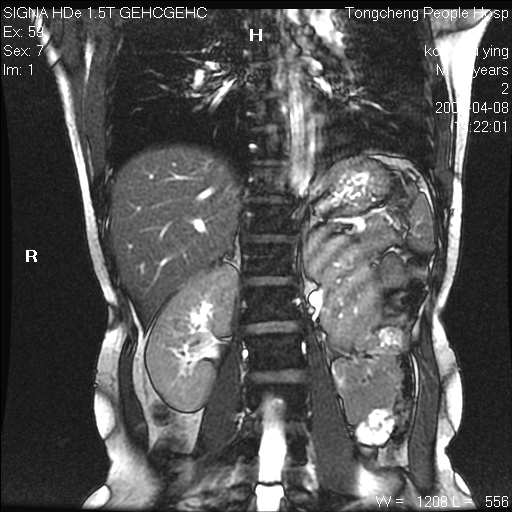

标题: CL1008:【经典】胆囊石榴籽样结石。

女,41岁。健康体检——彩超提示:胆囊显示不清。平素健康,无不适感。

腹部mr扫描及mrcp,图像如下: